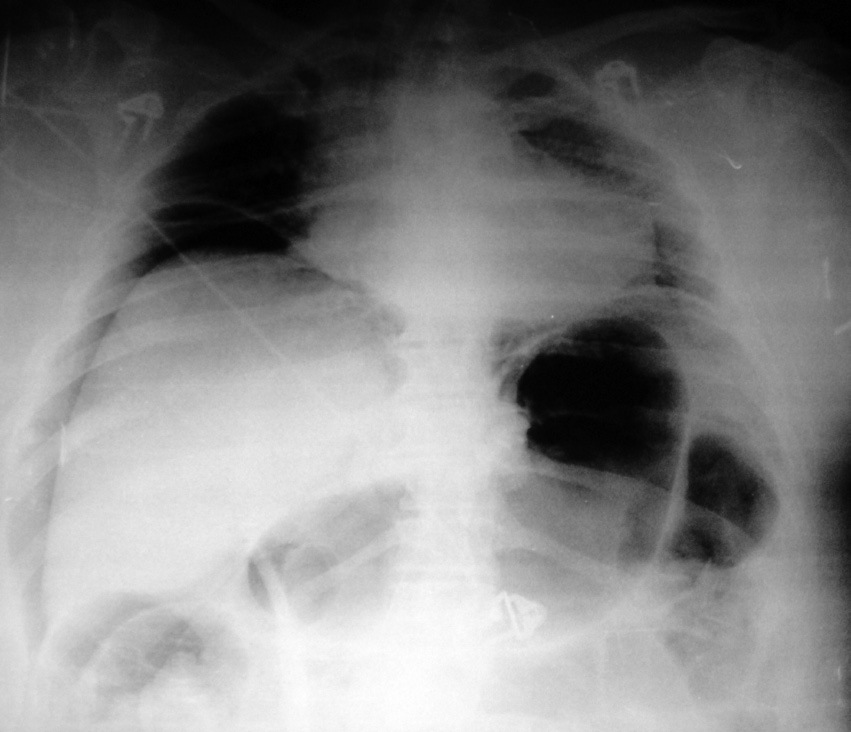

Las guías sobre el manejo del S.C.A. aconsejan un manejo quirúrgico desde cifras de 20-25 mm Hg, aunque condicionado a la repercusión clínica provocada8. Existe información bibliográfica de un cuadro denominado taponamiento abdominal agudo o neumoperitoneo a tensión; en estas referencias se recomienda considerar la necesidad de realizar una punción con aguja a través de la pared abdominal para una descompresión inmediata aún sin confirmación radiológica 9 ,10 . Es interesante que se haga referencia como base de un diagnóstico definitivo a la presencia radiológica de un desplazamiento medial e inferior del hígado, que nuestra paciente presentaba en la radiografía abdominal simple (Figura 1). En pacientes sometidas a dilataciones endoscópicas debe haber un elevado índice de sospecha de este cuadro y se debería incorporar la monitorización de la presión intraabdominal a la práctica habitual de las Unidades de Reanimación, como una herramienta sencilla y valiosa en nuestros algoritmos de toma de decisiones.

Figura 1 Imagen procedente de estudio digestivo gastroduodenal con contraste.